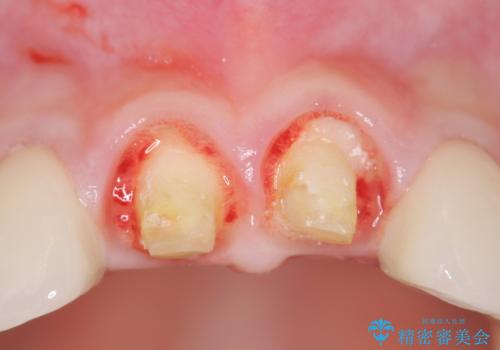

- 数ヶ月前に他院で装着したセラミッククラウンから、歯ブラシのたびに出血することの改善を求めて来院されました。

X線写真よりクラウンの際があっていない状態であることがわかり、再度精度の良いセラミッククラウンを製作していくこととなりました。

残存している歯と、クラウンの合いが悪い(不適合クラウン)歯汚れは溜まりやすく歯ぐきが腫れ虫歯・歯周病の再発リスクを高めます.